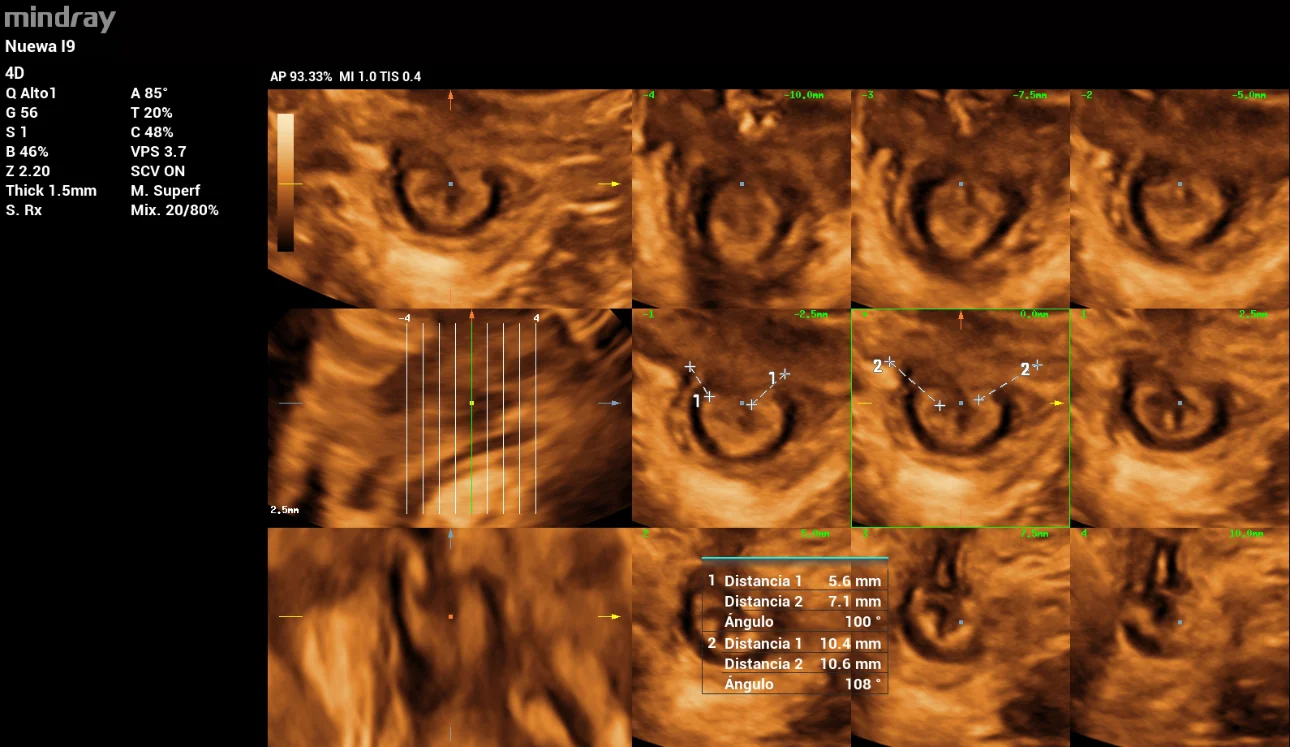

In the anal sphincter complex evaluation in 3D by the multi-slice tool, we found an External anal sphincter (EAS) with a defect of 108° in 4/6 of slides and an Internal anal sphincter (IAS) with a defect of 100° in 4/6 slides.

pelvic-floor-ultrasound-stress-incontinence-fig6

Figure 6: Evaluation of EAS & IAS with multi-slice tool iPage